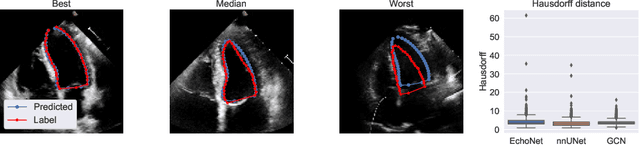

Abstract:Fully automatic cardiac segmentation can be a fast and reproducible method to extract clinical measurements from an echocardiography examination. The U-Net architecture is the current state-of-the-art deep learning architecture for medical segmentation and can segment cardiac structures in real-time with average errors comparable to inter-observer variability. However, this architecture still generates large outliers that are often anatomically incorrect. This work uses the concept of graph convolutional neural networks that predict the contour points of the structures of interest instead of labeling each pixel. We propose a graph architecture that uses two convolutional rings based on cardiac anatomy and show that this eliminates anatomical incorrect multi-structure segmentations on the publicly available CAMUS dataset. Additionally, this work contributes with an ablation study on the graph convolutional architecture and an evaluation of clinical measurements on the clinical HUNT4 dataset. Finally, we propose to use the inter-model agreement of the U-Net and the graph network as a predictor of both the input and segmentation quality. We show this predictor can detect out-of-distribution and unsuitable input images in real-time. Source code is available online: https://github.com/gillesvntnu/GCN_multistructure

Abstract:Accurate and consistent predictions of echocardiography parameters are important for cardiovascular diagnosis and treatment. In particular, segmentations of the left ventricle can be used to derive ventricular volume, ejection fraction (EF) and other relevant measurements. In this paper we propose a new automated method called EchoGraphs for predicting ejection fraction and segmenting the left ventricle by detecting anatomical keypoints. Models for direct coordinate regression based on Graph Convolutional Networks (GCNs) are used to detect the keypoints. GCNs can learn to represent the cardiac shape based on local appearance of each keypoint, as well as global spatial and temporal structures of all keypoints combined. We evaluate our EchoGraphs model on the EchoNet benchmark dataset. Compared to semantic segmentation, GCNs show accurate segmentation and improvements in robustness and inference runtime. EF is computed simultaneously to segmentations and our method also obtains state-of-the-art ejection fraction estimation. Source code is available online: https://github.com/guybenyosef/EchoGraphs.